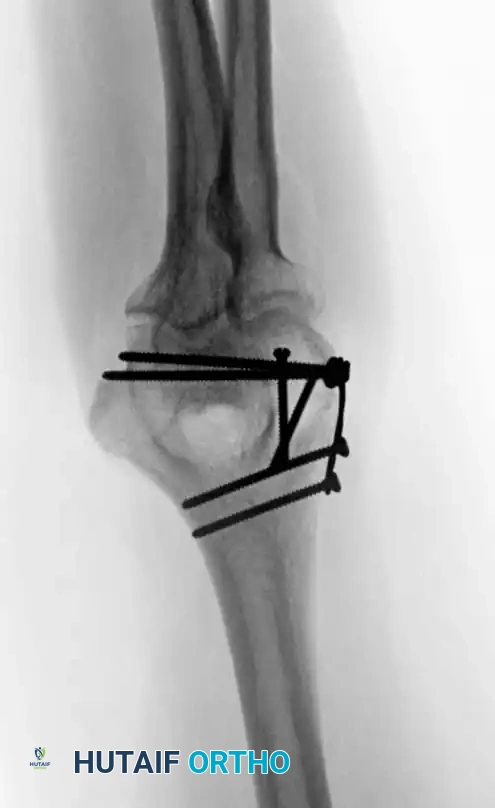

However, modern biomechanical studies (e.g., Self et al., Schemitsch et al.) have demonstrated that parallel plating (direct medial and direct lateral plating) provides superior resistance to torsional forces and axial loading, particularly in the presence of severe metaphyseal comminution. Precontoured anatomical locking plates have largely replaced one-third tubular and 3.5-mm reconstruction plates, which are prone to fatigue failure in complex patterns.

Image

Fig. 4: Distal humeral fracture with intra-articular extension managed with direct medial and lateral parallel plate fixation.